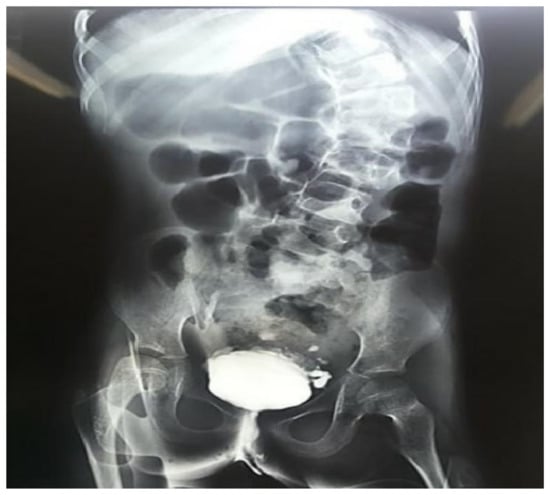

On a closer evaluation of the genitourinary system, the patient exhibited recurrent urinary tract infections, besides a variety of abnormal results on imaging and functional studies (Figure 4). In a renal scintigraphy with dimercaptosuccinic acid, the presence of horseshoe kidneys and relative renal function of 69% in the right kidney and 31% in the left kidney were verified. An ultrasonography of the kidneys and urinary tract and a voiding cystourethrography demonstrated findings of mild hydronephrosis, hydroureter and vesicoureteral reflux grade II on the right side.

Figure 4. Urinary urethrocystography evidencing marked scoliosis and signs of neurogenic bladder in a 10-year-old girl with trisomy 18 and Dandy-Walker Syndrome.